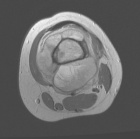

Patient is an 18 y/o female who presented c/o four month hx. of L. knee pain and swelling; she attended PT and x-rays revealed a lesion

PMH: unremarkable; PE: L. distal thigh w/ palpable warm mass; full PROM; NVI

Zoom image: Radiological image Radiological image.